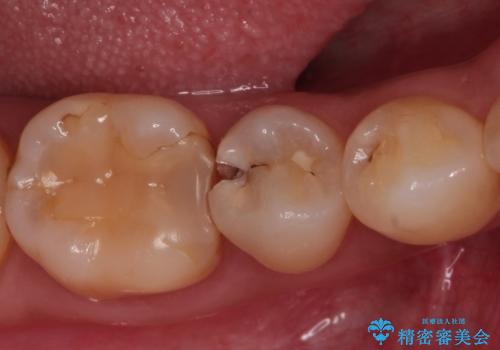

虫歯の治療 セラミックの詰め物で綺麗に